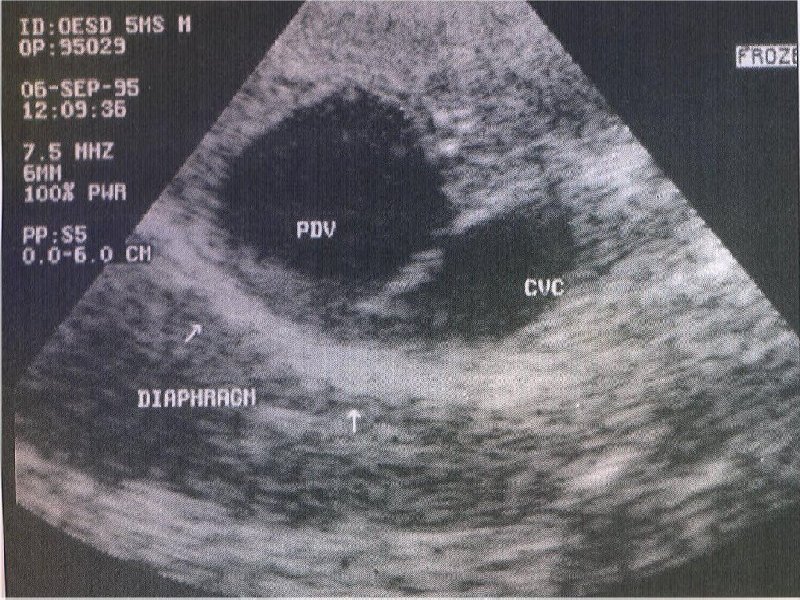

FIGURE 3

Ultrasound image of the liver from a dog with a portosystemic shunt. Note the

large anomalous patent ductus venous (PDV) adjacent to the caudal vena cava

(CVC) (photograph courtesy of P. Watson, University of Cambridge).